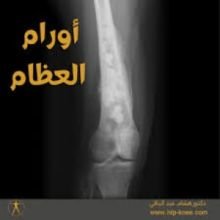

كتاب أورام العظام من تأليف عيسى سليم بن عمران .. أول كتاب من نوعه بالمكتبة الطبية في ليبيا وضعه المؤلف عام 2020 من خلال خبرته الطويلة في مجالي طب وجراحة العظام وكذلك الطب الفيزيائي أي الطبيعي ومن خلال تجربته خلال أكثر من 40 عاما مع تشخيص وعلاج أورام العظام التي وإن كانت بالنسبة للأورام الأخرى في جسم الانسان نادرة الحدوث إلا أها يمكن أن تكون خطيرة ومدمرة وقاسية الأثر على كافة الأعضاء الأخرى.